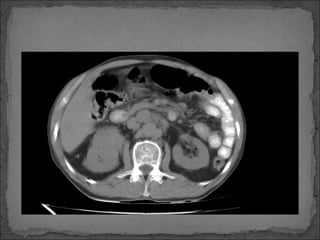

Paciente de 50 años de edad, con historia de Ca renal

diagnosticado hace 6 meses, quien súbitamente inicia

con dolor en cuadrante superior izquierdo hace 6 horas

por lo que consulta.

Facultativo le solicita una TC abdominal y luego refiere a

paciente a este centro hospitalario.